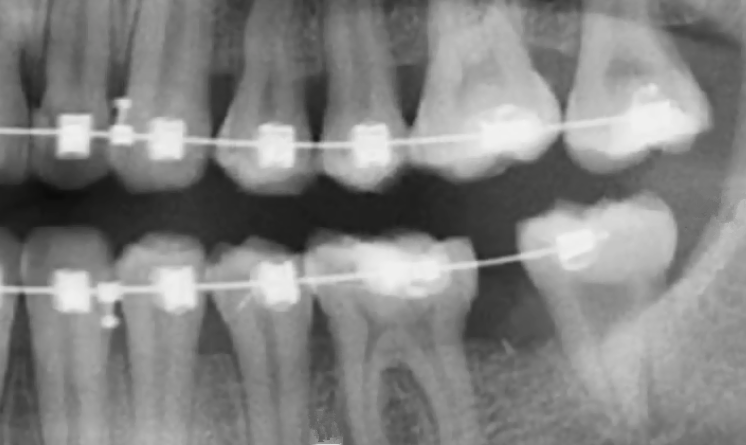

不過,有一種情況比較特殊:如果磨牙有牙齒缺失或者是齲壞嚴(yan) 重,而立世牙健康完整,可以通過正畸牽引出來當做磨牙來使用的話,這就是屬於(yu) 廢物利用了,是需要盡量支持的。但是需要事先找正畸醫生評估是否可以牽引成功。

一般來說,不用拔除的立世牙,通常如下圖所示,要麽(me) 是極少數出現的堂堂正正有上下牙,而且位置正,可以發揮咀嚼作用;要麽(me) 是上麵的特殊情況,可以牽引出來替代磨牙使用的;再者就是完全埋伏在牙床內(nei) ,不影響鄰牙以及周圍組織,這樣的也可以暫時觀察。

牽引成功替代磨牙的智齒